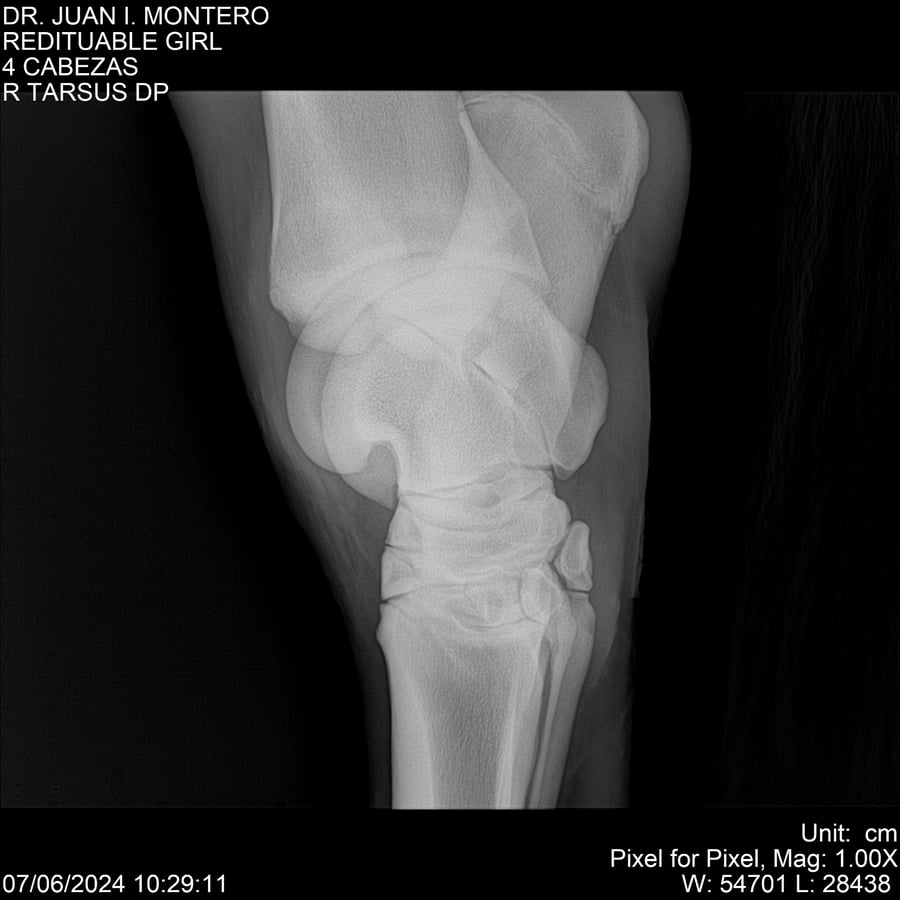

LOTE 19, REDITUABLE GIRL Lote Anterior Volver al remate Lote Siguiente Ficha Contacto Montevideo - Ficha del Lote Identificador: #281096 Categoría: Yeguarizos Montevideo - 79 Visualizaciones ClicData Contacto Empresa: Abelenda N. R., Walter Hugo Nombre*: Teléfono* : E-mail* : Mensaje Enviar Registrese gratis Este contenido Exclusivo está disponible sólo para usuarios registrados Ingresar